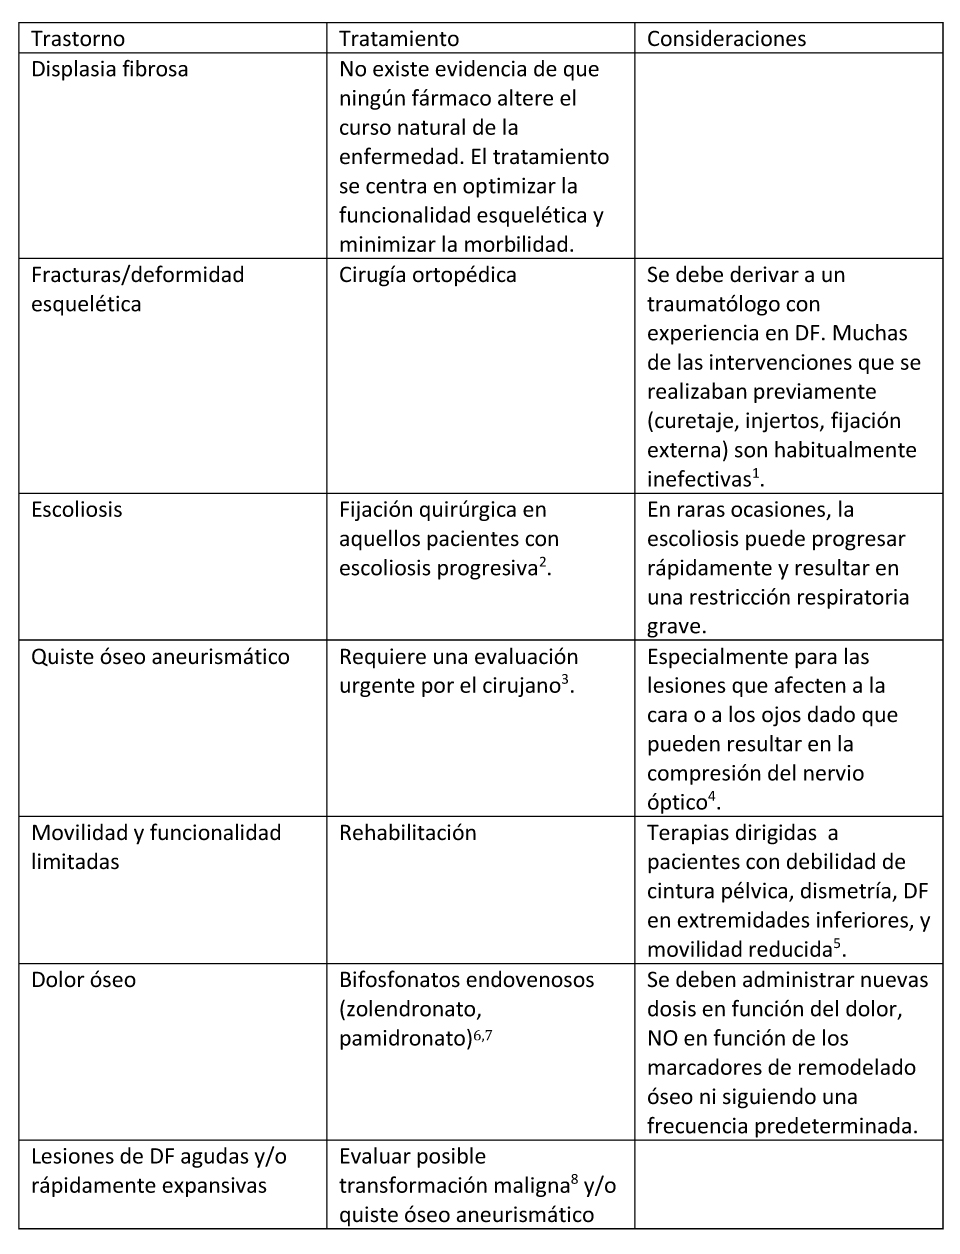

Tratamiento de las manifestaciones

Tabla 3. Evaluaciones Recomendadas tras el Diagnóstico Inicial en Individuos con Displasia Fibrosa/Síndrome de McCune-Albright

- Stanton et al 2012, Leet et al 2016

- Leet et al 2004b, Mancini et al 2009

- Leet et al 2012, Manjila et al 2013

- La descompresión profiláctica del nervio óptico para reducir el riesgo de pérdida visual está contraindicada ya que de hecho aumenta el riesgo de pérdida visual: Leet et al 2002, Cutler et al 2006, Amit et al 2011.

- Paul et al 2014.

- El tratamiento con alendronato oral no es efectivo para el control del dolor óseo (Boyce et al 201)